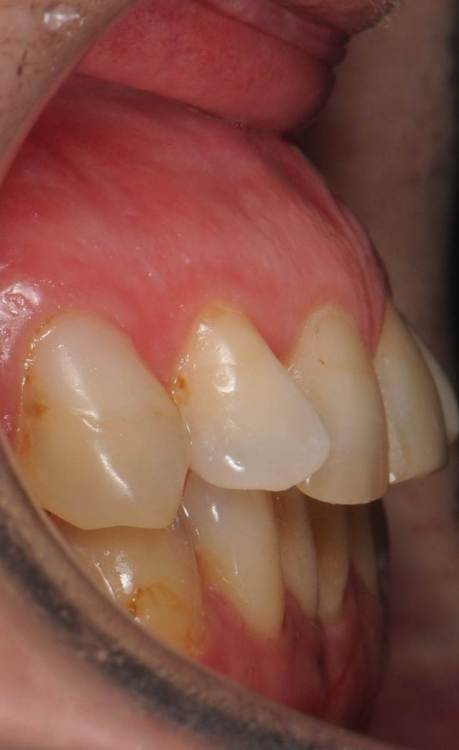

До:

Закончил тотал и решил поделиться. Протезировали с учетом положения ВНЧС в концепции Славичека.  В конце изготовление брукс чекеров для проверки нежелательных контактов во время сна.  Гигиену пытаемся победить...